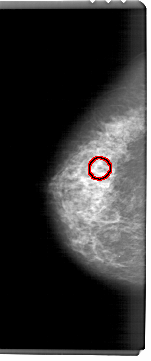

A_1461_1.LEFT_CC

LEFT_CC LINES 6856 PIXELS_PER_LINE 2851 BITS_PER_PIXEL 12 RESOLUTION 43.5 OVERLAY

FILE: A_1461_1.LEFT_CC.OVERLAY

TOTAL_ABNORMALITIES 1

ABNORMALITY 1

LESION_TYPE CALCIFICATION TYPE AMORPHOUS DISTRIBUTION CLUSTERED

ASSESSMENT 4

SUBTLETY 4

PATHOLOGY BENIGN

TOTAL_OUTLINES 1

BOUNDARY